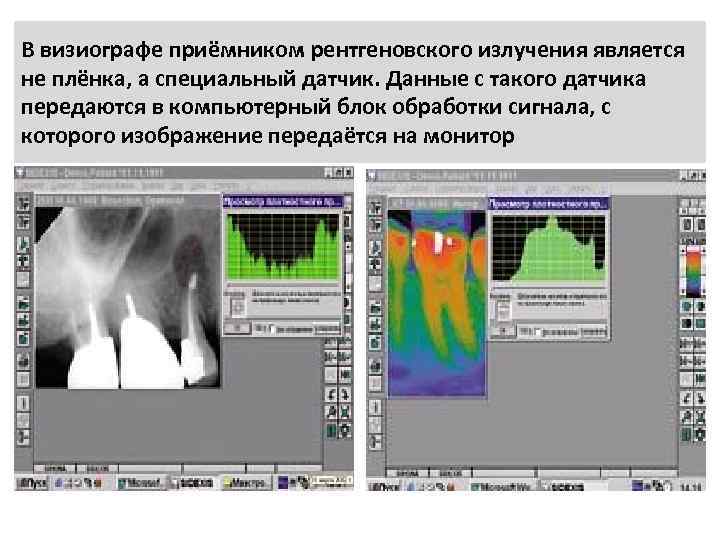

В визиографе приёмником рентгеновского излучения является не плёнка, а специальный датчик. Данные с такого датчика передаются в компьютерный блок обработки сигнала, с которого изображение передаётся на монитор

C помощью программного обеспечения можно максимально изучить рентгеновский снимок : измерить длину каналов, сделать инверсию (отобразить чёрно-белый снимок в бело-чёрный), сделать рельеф и тогда можно увидеть объект объёмным.